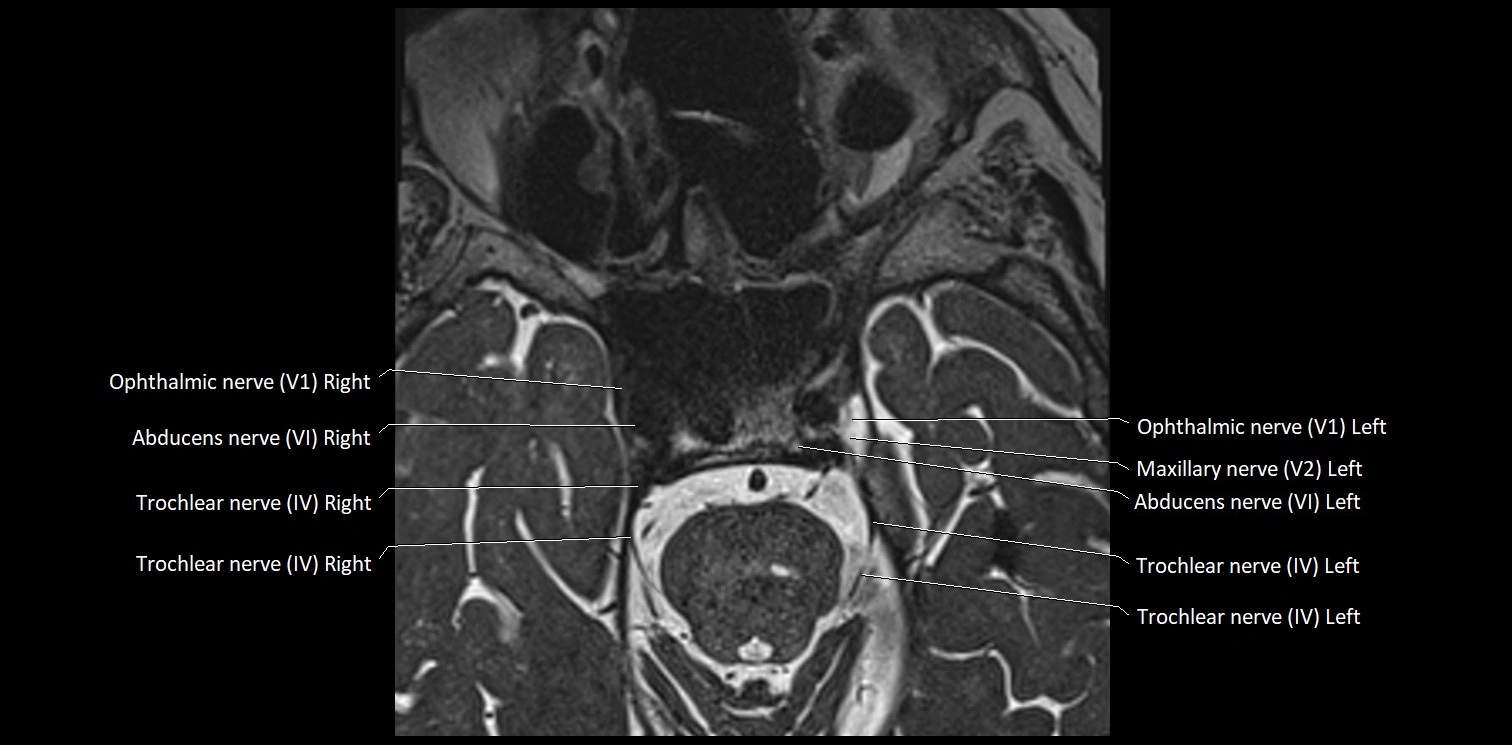

MRI Appearance

• The abducens nerve is a small, thin, linear structure

• Best visualized on high-resolution T2-weighted 3D MRI sequences (e.g., FIESTA or CISS)

• Seen as a hypointense (dark) line running from the brainstem at the pontomedullary junction, traversing the prepontine cistern, and entering Dorello’s canal under the petrosphenoidal ligament, then into the cavernous sinus, and finally the orbit

• May be challenging to visualize in standard MRI due to its small size

• Pathology may be inferred by absence, displacement, or enhancement of the nerve

MRI images

image